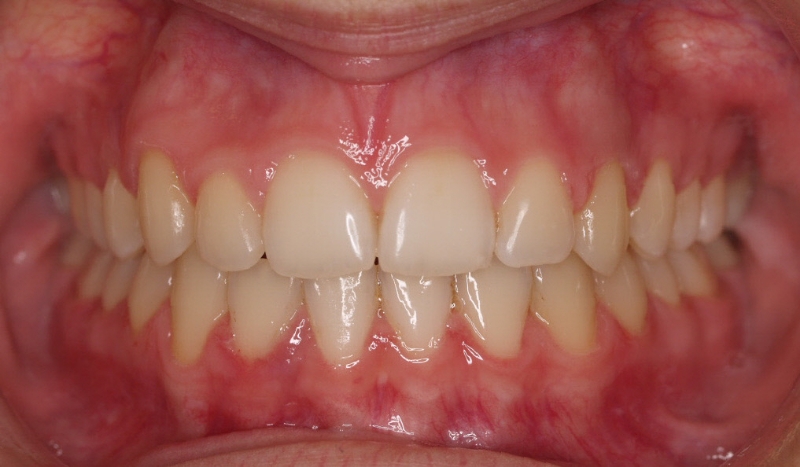

La paciente O.O. acude a nuestra consulta por:

– Canino 13 e incisivo lateral 42 en posición ectópica.

– Canino 23 incluido.

Con lo que decide realizarse un tratamiento de ortodoncia de duración de 24 meses con brackets damon Q.

CASO COMPLETO: